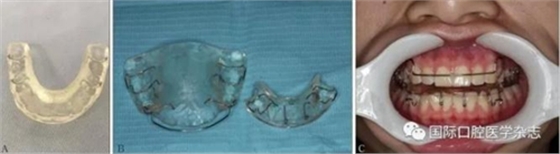

3.1.2 咬合板治療[16]

咬合板治療的適應(yīng)證:顳下頜關(guān)節(jié)紊亂病。初診時(shí)取患者上下頜牙列印模和咬合記錄,牙模及咬合記錄送至同一加工廠制作牙合墊,牙合墊后牙區(qū)墊高3 mm。2周后復(fù)診佩戴,囑患者夜間佩戴,佩戴時(shí)間為每天10~12 h,連續(xù)佩戴3個(gè)月,治療期間,每月復(fù)診1次,調(diào)整咬合干擾(圖16)。

A:穩(wěn)定牙合墊;B:Twin-block牙合墊;C:患者帶入Twin-block牙合墊。

圖 16 咬合板治療